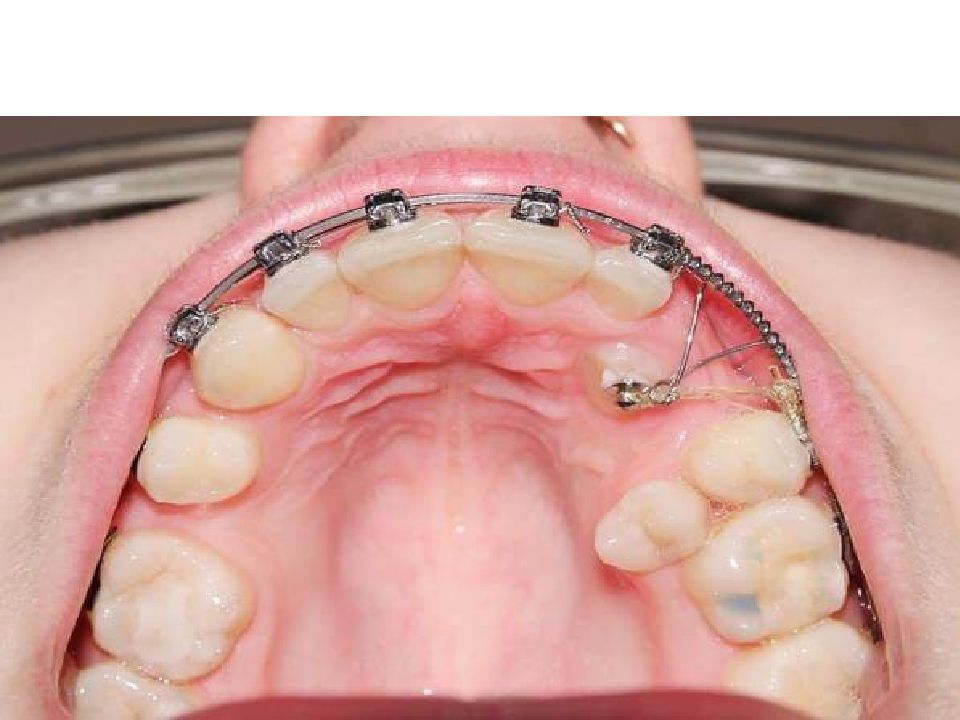

Лечение комплексное. Оно проводится в амбулаторных условиях: первичная хирургическая обработка гнойного очага сочетается с комплексной противовоспалительной терапией (антибактериальные препараты, нестероидные противовоспалительные препараты, антигистаминные препараты). Хирургическое лечение перикоронита. При наличии достаточного места в зубной дуге для прорезывания зуба и правильной его пространственной ориентации наиболее предпочтительной является операция - перикоронарэктомия - полное иссечение слизистой оболочки вокруг коронки зуба мудрости, позволяющее обнажить не только жевательную, но и боковые поверхности коронки. Операцию проводят под проводниковой и инфильтрационной анестезией. Слизистую оболочку иссекают изогнутым скальпелем или ножницами. Также возможно применение лазера, электроножа (коагулятора), криодеструкции. При невозможности полностью обнажить жевательную и боковые поверхности зуба по причине его дистопии проводится оперативное вмешательство - перикоронаротомия - рассечение слизистой оболочки над коронкой зуба, позволяющее обнажить поверхность зуба, расположенную под слизистым капюшоном (медиальная, дистальная, язычная, вестибулярная)

Слайд 21: Лечение!